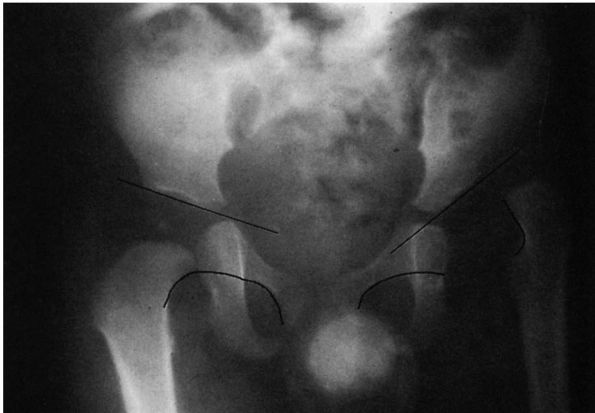

Radiographically, however, the major difference between dysplasia and

subluxation is the intactness of the Shenton line (Figure 15-7).

In subluxation, the Shenton line is disrupted, and the femoral head is

superiorly or laterally displaced from the medial wall of the

acetabulum. In dysplasia, the normal Shenton line relation is intact.

![]() |

|

FIGURE 15-7.

Radiographically, the major difference between dysplasia and subluxation is the intactness of the Shenton line. The right hip is dysplastic (Shenton line intact). The left hip is subluxated (Shenton line disrupted). All subluxated hips are, by definition, dysplastic. (Weinstein SL. Natural history of congenital hip dislocation [DDH] and hip dysplasia. Clin Orthop 1987;225:62-76) |